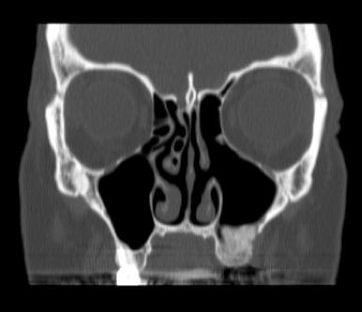

| A 51 year old female presents with one year of left facial & tooth pain, left nasal obstruction, postnasal drainage and headaches. Past dental history is significant for RCT of teeth 10 & 11, apicoectomy of tooth #10, and dental implants #12 & 13. The implants failed and she developed an oral antral fistula after removal of the implants and debridement of necrotic bone. Coronal CT image demonstrating severe left maxillary and ethmoid sinus disease. This one sided sinus disease was of odontogenic origin. |

|

| A coronal CT 2 months after ethmoid and maxillary sinus surgery showing complete resolution of sinus disease. |